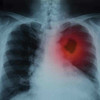

Akciğer dokusundaki normal hücreler kontrol dışı çoğalarak kitle yani tümör oluşturduğunda akciğer kanseri meydana geliyor. Kitle büyüyerek önce çevre dokulara, dolaşım yoluyla da beyin, karaciğer gibi diğer organlara yayılıyor. Akciğer kanserinin erken dönemde belirti vermeyebileceğini ifade eden Göğüs Hastalıkları Uzmanı Dr. Aygün Gür, “Geçmeyen ve giderek artan öksürük, öksürükle ağızdan kan veya kanlı balgam çıkarmak, nefes darlığı, göğüs ağrısı, ses kısıklığı, halsizlik, iştahsızlık, geçmeyen ve tekrarlayan akciğer enfeksiyonu gibi belirtiler görülebilir.” Dedi.

Tanı için akciğer röntgeni, bilgisayarlı tomografi gibi görüntüleme yöntemleriyle kitle saptandıktan sonra, kitleye hangi yolla ulaşarak örnek alınacağı belirleniyor. Kanserin türü ve evresi belirlendikten sonra tedavinin planlandığını belirten Gür, “Akciğer kanserinde erken tanı çok önemli. Tedavi şansını artırdığı gibi ölüm oranını da azaltmaktadır. Tedavi; hastanın yaşı, klinik durumu, kanserin tipi, evresi gibi faktörler ışığında planlanarak cerrahi, kemoterapi veya radyoterapi programlarının biri veya birkaçı bir arada uygulanır” diye konuştu.